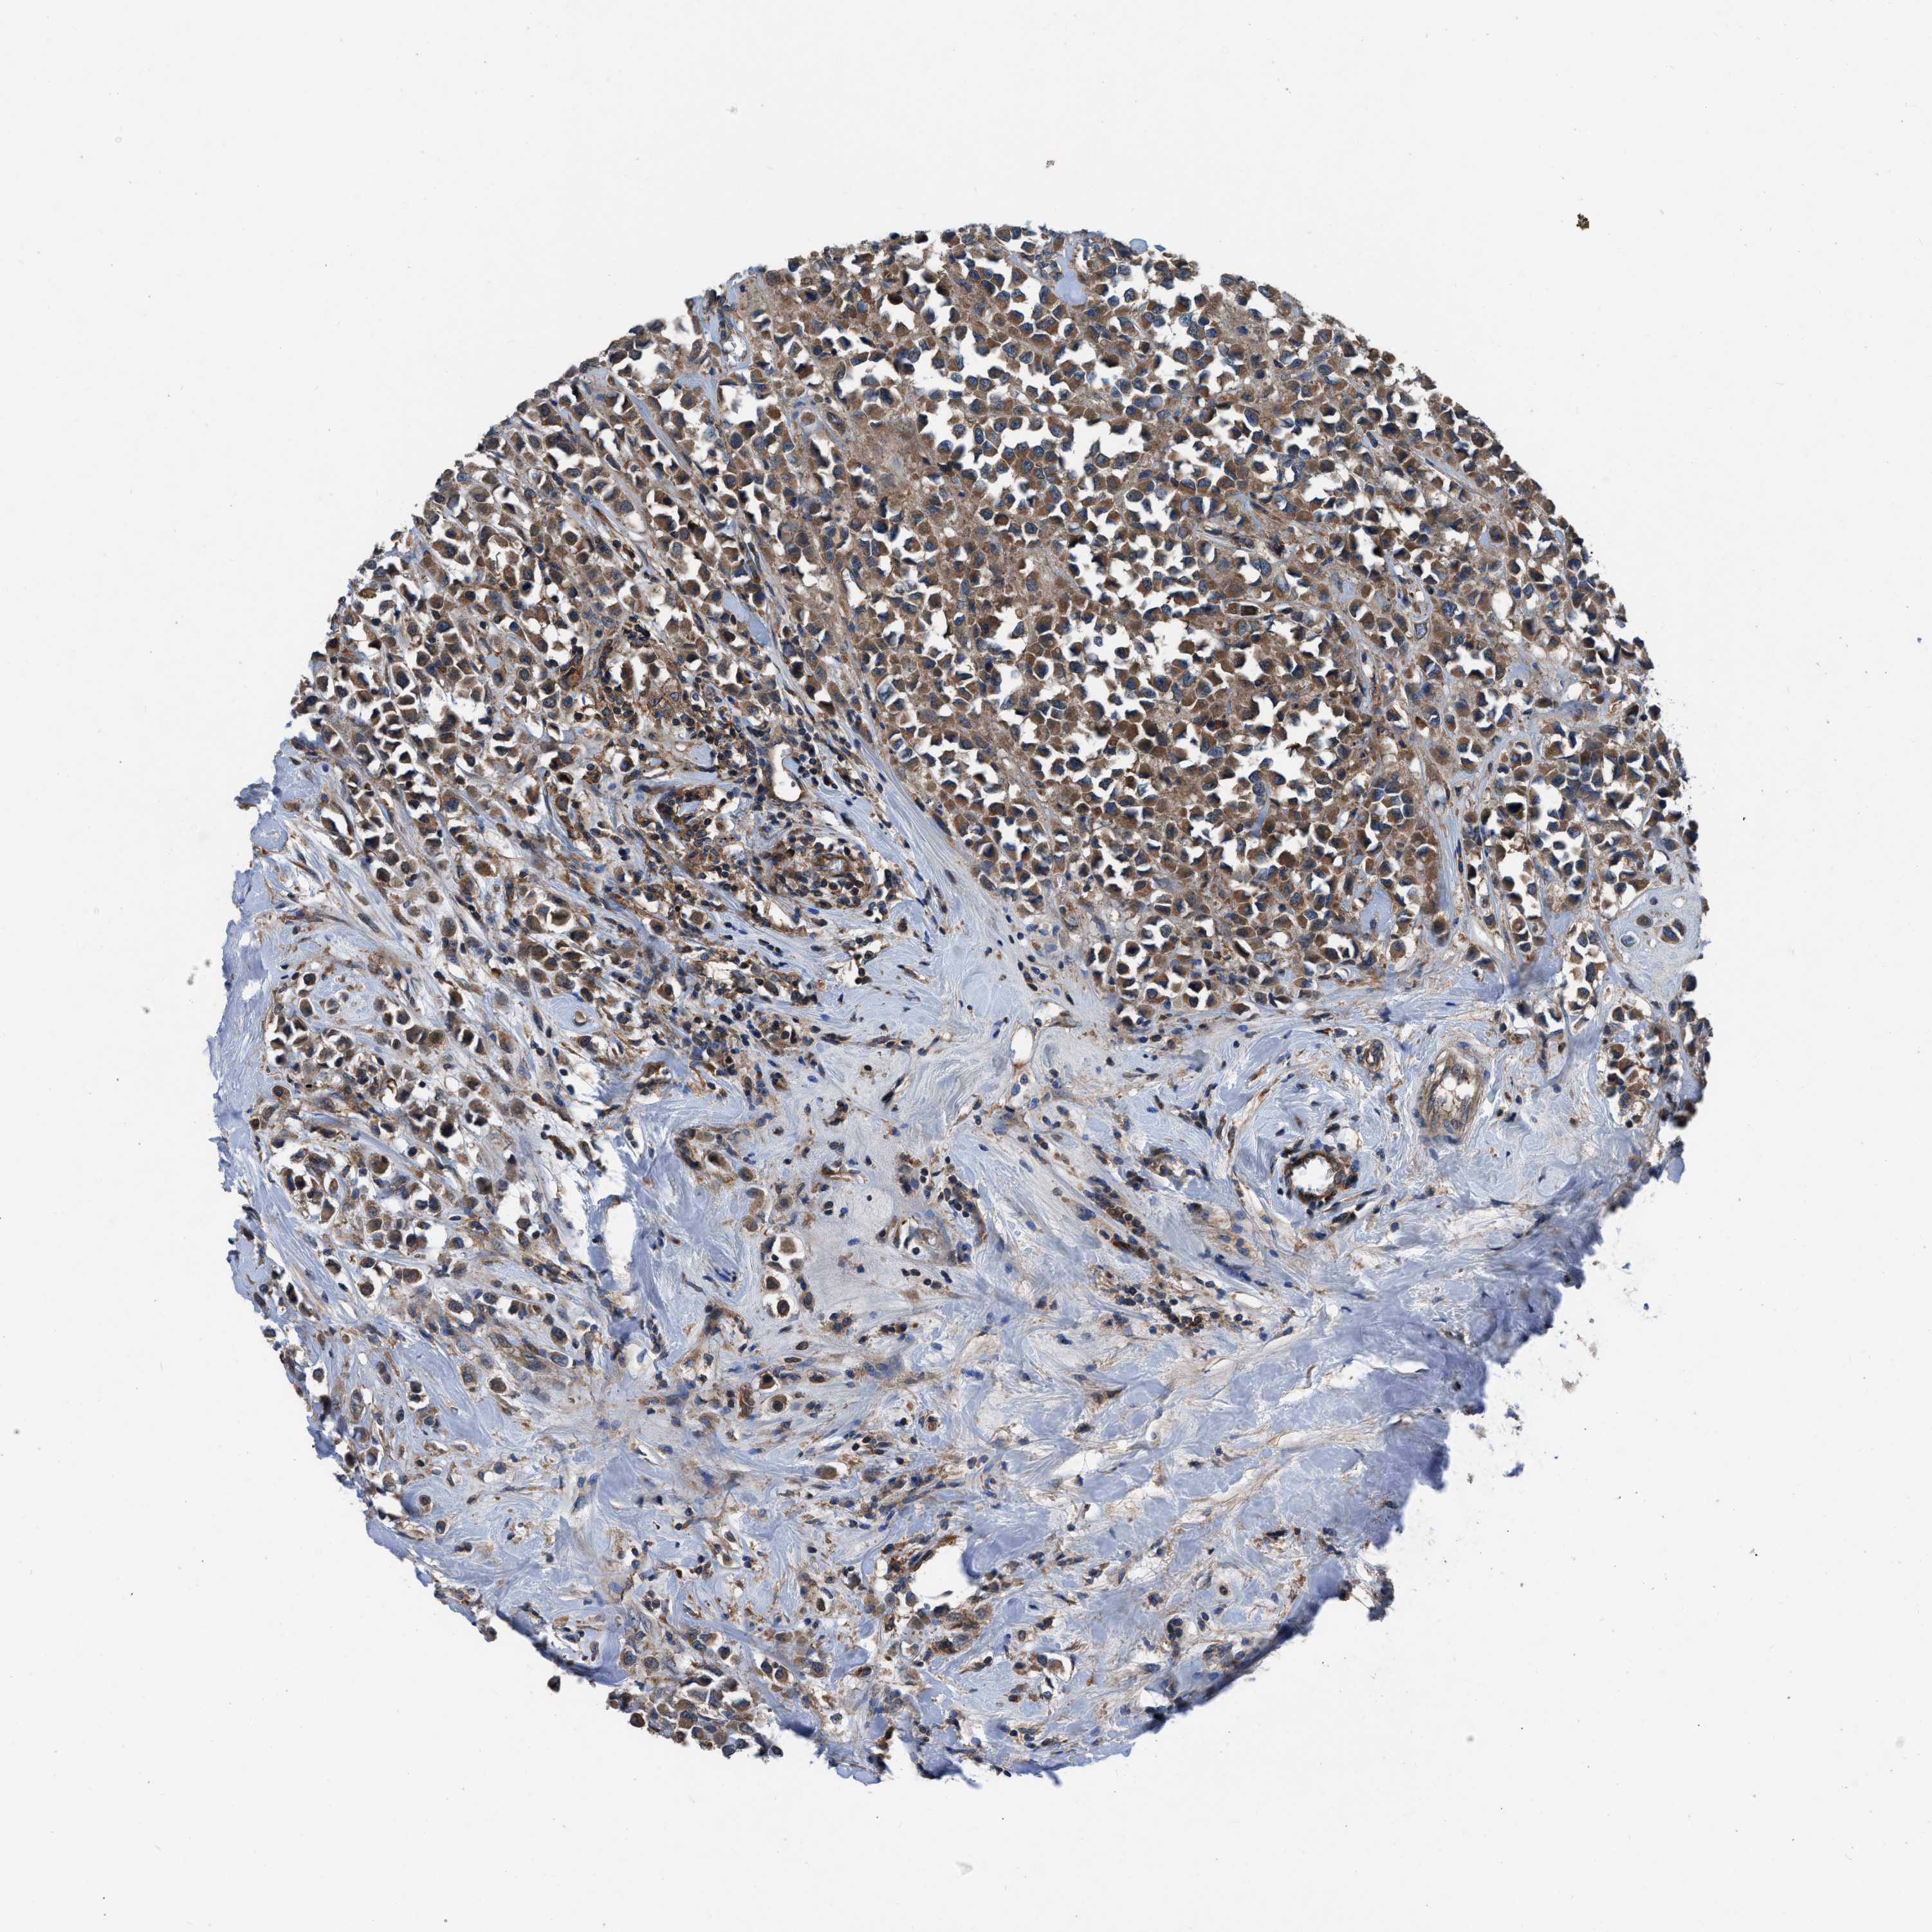

CANCER BREAST CANCER Show tissue menu

BRCA TCGA BRCA VALIDATION PROTEIN EXPRESSION